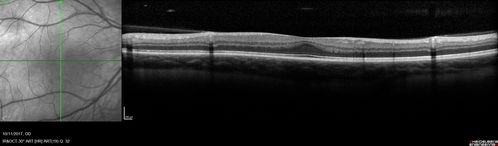

Foveal Hypoplasia in adult with ROP - good Vision

26 year old female Born at 1 lb 15 oz and had cryo for ROP at birth.

VA OD: Dcc20/25

VA OS: Dcc20/20

SD OCT shows foveal hypoplasia

The SD OCT scan shows incursion of one or more of the plexiform layers into the center of the fovea.